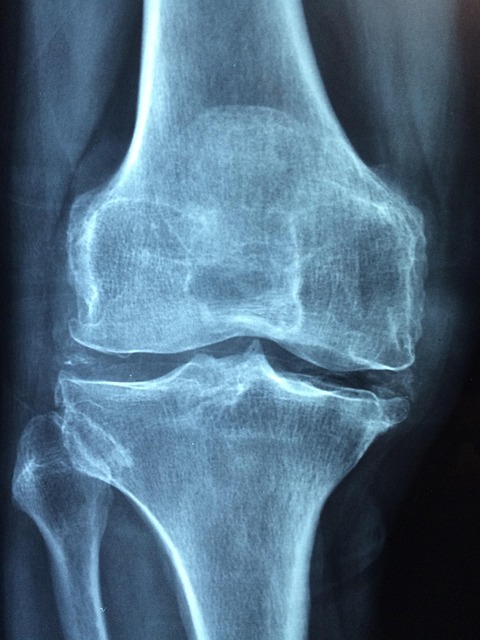

고관절은 걷기, 뛰기, 앉기 등 거의 모든 움직임에 관여하며 체중을 직접 지탱합니다. 연골 손상, 근육 불균형, 점액낭 염증, 과사용 등이 주요 원인입니다. 고관절 내부는 연골·관절막·Labrum·근육·힘줄이 밀집되어 있어, 어디가 문제인지에 따라 고관절 통증 증상이 달라집니다. 사타구니 당김은 내부 구조 문제, 옆쪽 통증은 점액낭 문제, 찝힘은 충돌증후군과 관련 있을 가능성이 높습니다.

3. 질환별 고관절 증상 비교표

| 고관절 점액낭염 | 엉덩이 옆쪽 | 눌렀을 때 통증 증가 |

| FAI 충돌증후군 | 사타구니 | 굽힘·내회전 시 찝힘 |

| Labrum 파열 | 사타구니, 소리 | 젊은 층 많음 |

| 퇴행성 고관절염 | 전반적 | 아침 뻣뻣함, 보행 통증 |

| 외측 통증 증후군 | 허리~엉덩이 | 코어 약화 관련 |